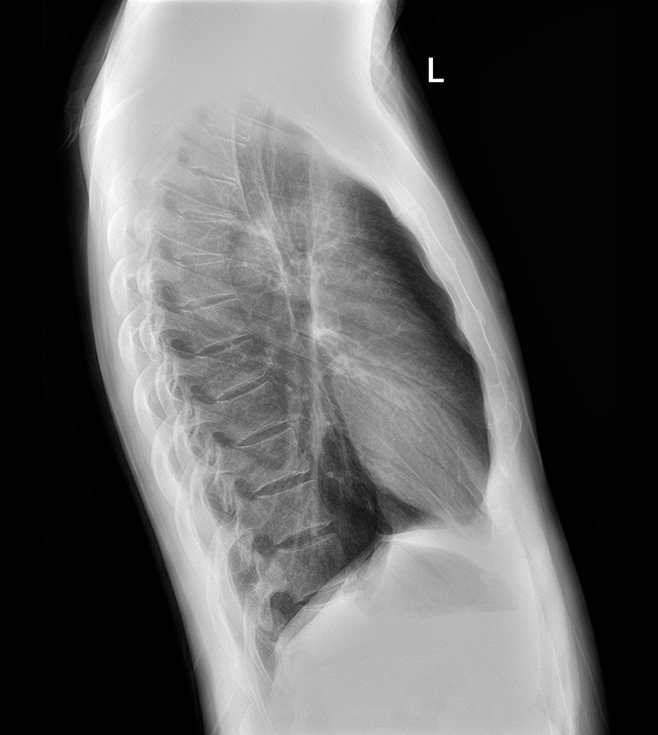

高清動態平板探測器

搭載自主研發超清大視野動態平板探測器,600微米碘化銫大幅提升X線轉化效率,獨特的非晶硅陣列與高速讀取集成電路緊密協作,輕松實現多幀率透視與高清點片。

17x17英寸

大幅面成像 -

900萬

高清像素點片 -

0.8S

動靜態切換 -

DFP同步曝光

高效暗噪聲抑制 -

線性探測平面

圖像無畸變、無失真